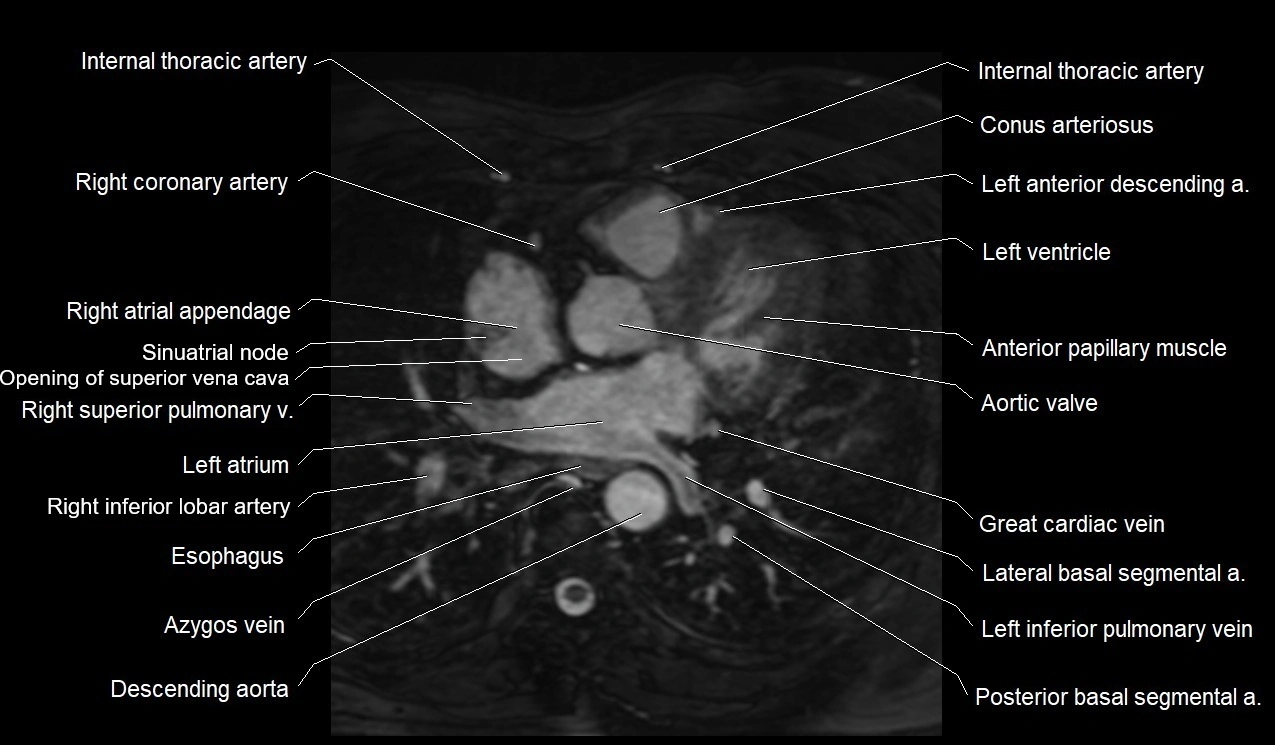

MRI image